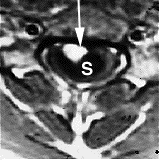

There are two tests that can provide a definite diagnosis of myelomalacia; magnetic resonance imaging (MRI), or myelography. Magnetic resonance imaging (MRI) is a medical imaging technique used in radiology to visualize the internal structure of the body used in the diagnosing of myelomalacia.[8] Certain MRI findings can detect where bone density and matter has been lost in people with spinal cord injuries. Diffuse hyperintensity appreciated on T2-weighted imaging of the spinal cord can be an indication of the onset or progression of myelomalacia